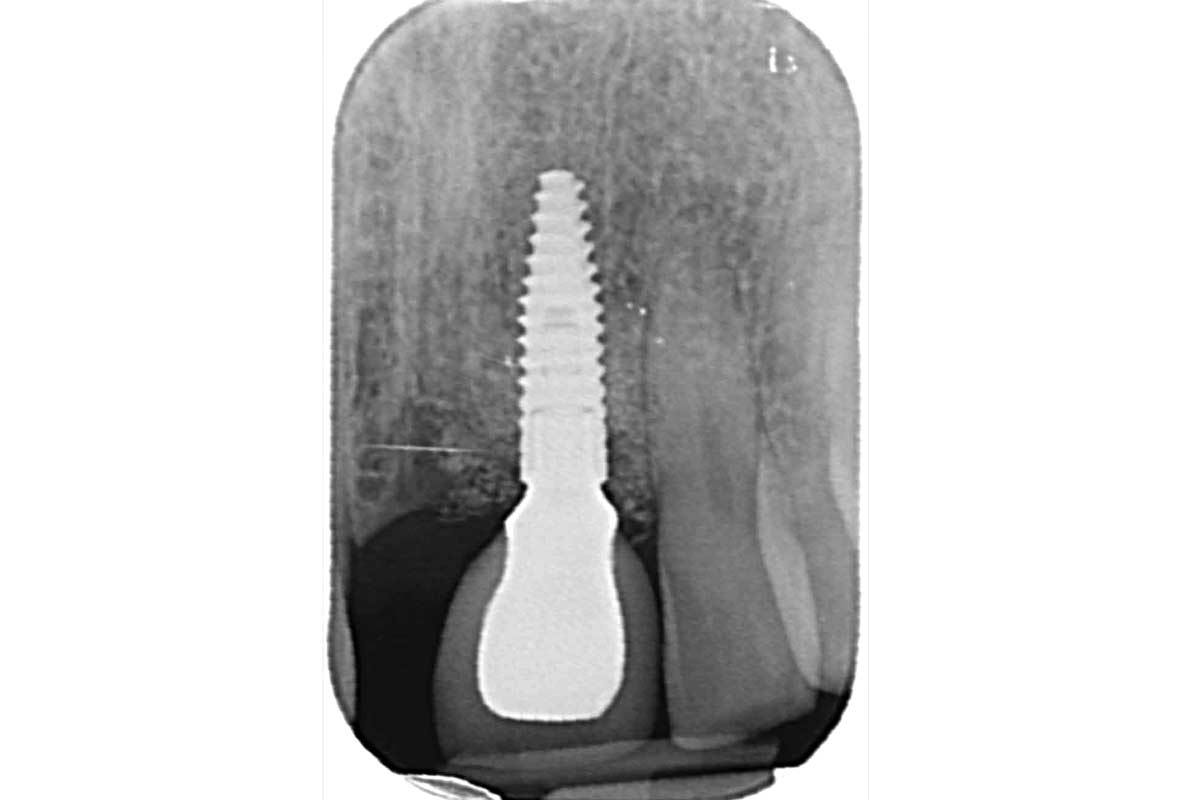

20/32 - postoperative X-rayBone augmentation in the aesthetic zone with maxgraft® bonering – Dr. R. Cutts

3/32 - Preoperative X-rayBone augmentation in the aesthetic zone with maxgraft® bonering – Dr. R. Cutts